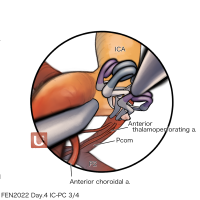

FEN2022シリーズ